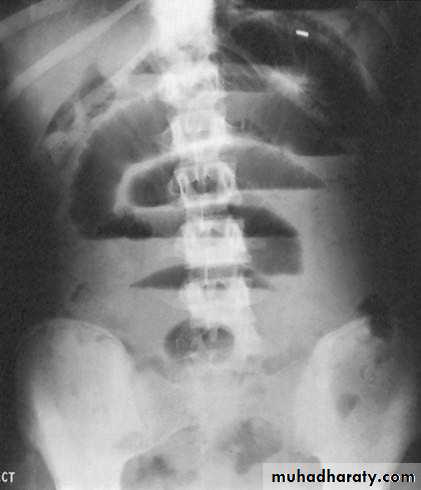

- upright films: dilated small bowel loops (>3 cm in diameter), air-fluid levels, and a paucity of air in the colon.

Small bowel obstruction

-The dilated bowel loops centrally located and lie transversely.-No/minimal gas is seen in the colon.

-valvulae conniventes,which completely pass across the width of the bowel

-ladder pattern

Multiple air fluid level, small and centrally located.